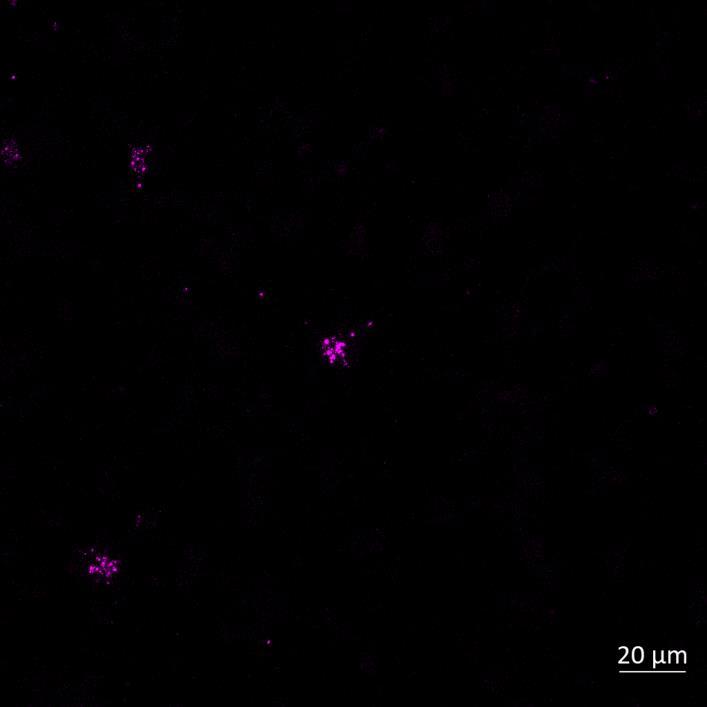

Live imaging showing progressive accumulation of Alexa Fluor 594labelled α-synuclein PFFs in cell bodies (PFF-positive neurons shown by arrows) of the “acceptor” chamber of microfluidics device over time